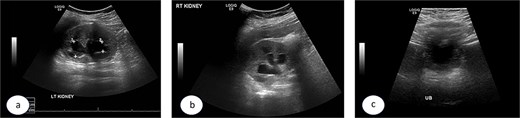

A 7-year-old child was referred to the pediatric urology clinic due to a history of recurrent febrile urinary tract infections and urge incontinence, accompanied by constipation (Bristol 2). These symptoms persisted despite meticulous conservative management, including urotherapy. Ultrasound (US) revealed bilateral pelviectasis and voiding cystourethrogram (VCUG) revealed bilateral Grade 3 VUR and a mildly trabeculated bladder wall, whereas the urethra appeared normal (Fig. 1a–d). A DMSA renal scan verified bilateral renal scarring, revealing differential renal function of 40% in the right kidney and 60% in the left kidney (Fig. 1e). Endoscopic intervention was warranted, and 1 ml of Deflux was injected on the left side and 0.6 ml on the right side, successfully creating an adequate mound. The patient was discharged in stable condition for several hours following surgery, despite being anuric. Subsequently, the patient experienced intense abdominal pain and was admitted to the emergency department. The physical examination was uneventful, except for moderate hypertension. The urinalysis revealed microscopic hematuria. His urea level was 16 mmol/L, and creatinine rose to 126 umol/L from a baseline of 40 umol/L. Post operative US at emergency room demonstrated increased bilateral hydronephrosis (Fig. 2).

Ultrasound images showing the left (a), and right (b) kidneys and the urinary bladder (c). VCUG is showed bilateral grade 3 VUR (d). DMSA images are shown in (e).